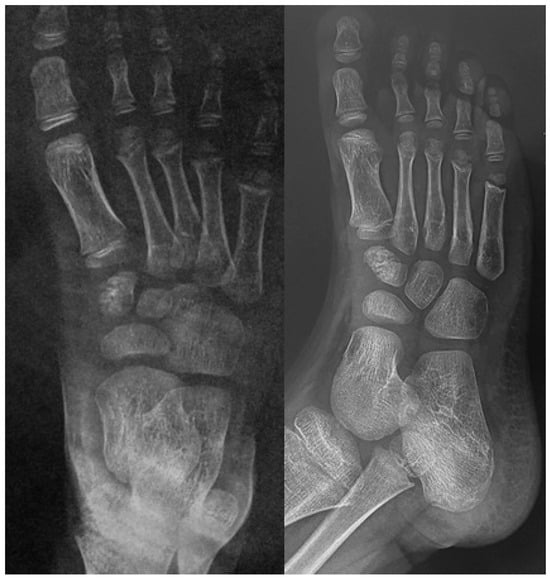

While the clinical findings can strongly suggest the presence of osteochondrosis, imaging is crucial for confirming the diagnosis and determining the extent of bone involvement.

Plain radiographs are the cornerstone of imaging in the diagnosis of lesser metatarsal osteochondrosis. In the early stages of the disease, when supported by a suggestive clinical presentation, obtaining a comparative radiograph of the contralateral foot can be a useful diagnostic tool (Figure 9).

Figure 9.

Radiograph of a symptomatic 10-year-old female patient showing early sclerosis and flattening of the second metatarsal head on the left foot, compared to the contralateral side.

In the later stages, radiographs may reveal characteristic changes including subchondral sclerosis, fragmentation, and flattening of the affected metatarsal head (Figure 10 and Figure 11). In some cases, the presence of joint space narrowing or bony irregularities may also be observed. However, early changes, such as bone marrow edema or subtle cartilage damage, may not be visible on standard radiographs. MRI is particularly useful in the early stages of the disease, as it can detect bone marrow edema, which is a sign of active bone inflammation and necrosis, even before structural changes become apparent on radiographs (Figure 10, Figure 11 and Figure 12).

If not promptly identified and adequately treated, the condition may progress to severe deformities in adulthood (Figure 13).

Figure 13.

The radiographic progression of the second metatarsal head osteochondrosis in a 22-year-old female patient who had not received any treatment.